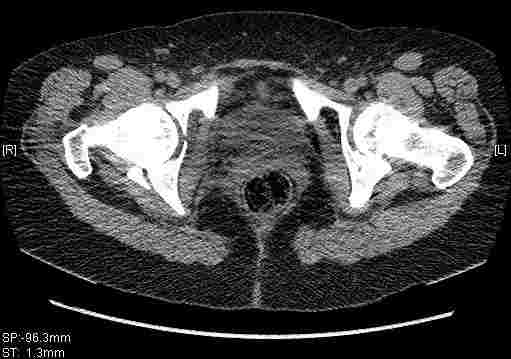

Re: Т-образный перелом вертлужной впадины

Удалось сегодня вывести пациентку в соседнюю больницу, где есть кт. Срезы сделаны только горизонтальные.